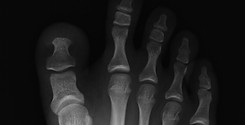

外反母趾(がいはんぼし)

外反母趾とは、親指が人差し指側に「く」の字状に曲がった状態の事をいいます。

原因は様々で必ずしもヒールをはいたから発症する病気ではありません。

遺伝的影響として、足の形や足趾間の靭帯・筋肉の緩みや弱さなどによる軟部組織のアンバランスなども考えられます。